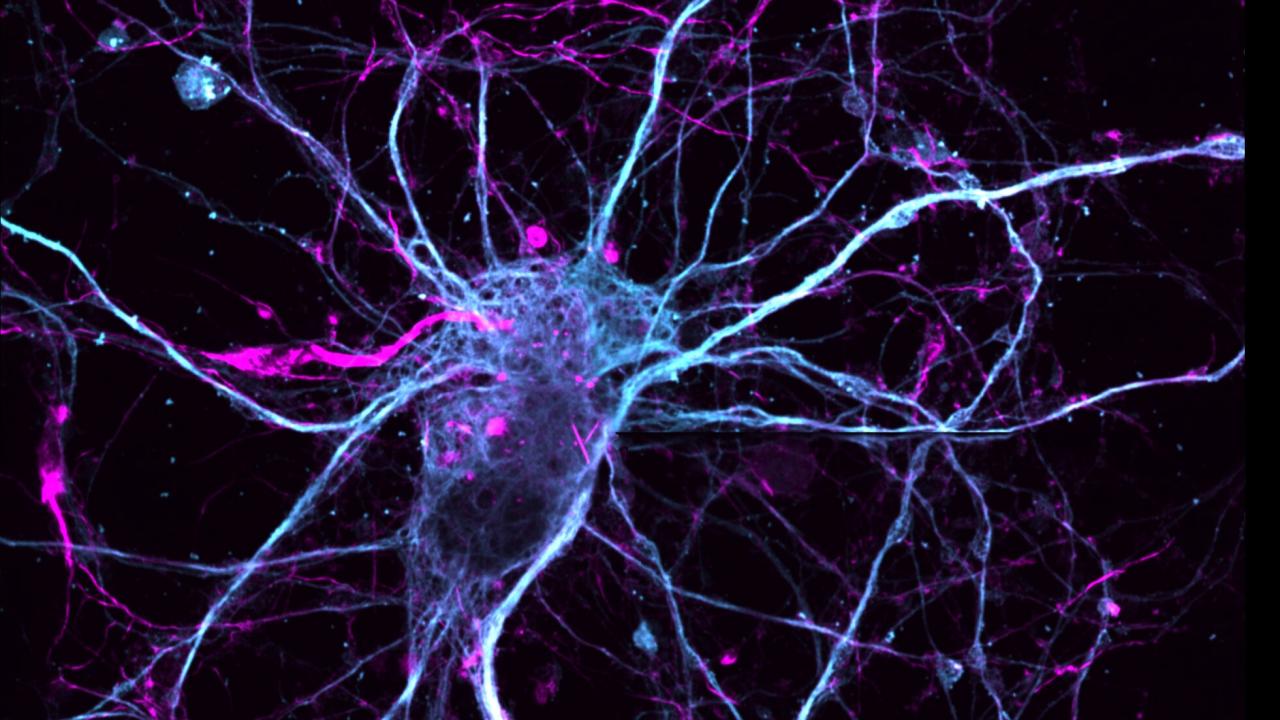

When the researchers tested the effects of ibogaine and its mirror image compound on neurons, they discovered that only the natural one promoted neuronal growth.

The second analogue of interest was (-)-10-fluoroibogamine. During experiments, the compound exhibited exceptional effects on neuronal structure and function, promoting growth and reconnection. Additionally, it showcased powerful effects on serotonin transporters, which are proteins that regulate serotonin levels at synapses.